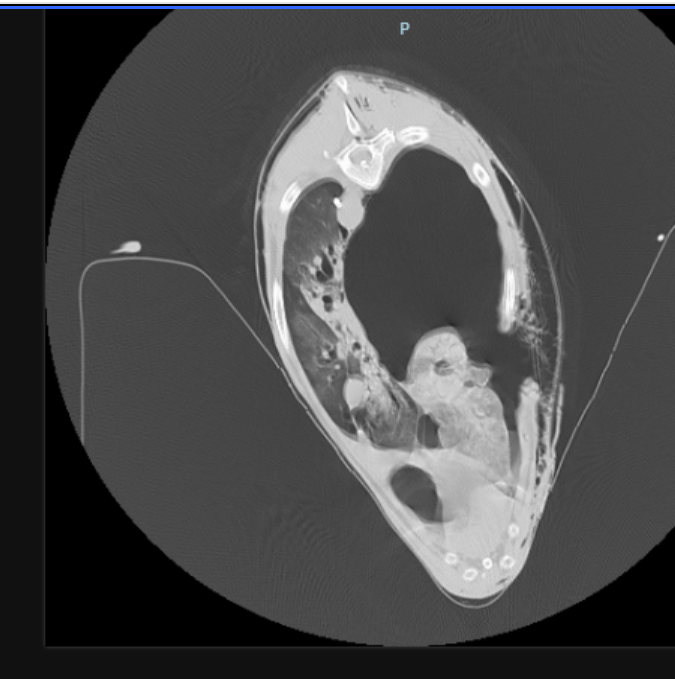

He suffered massive trauma, a serious pneumothorax, a punctured muscle wall, broken ribs and a punctured lung. Zach was dying and went into surgery at 10pm at night. Now, he is mostly stable but may need more surgery if he is leaking air into his chest.